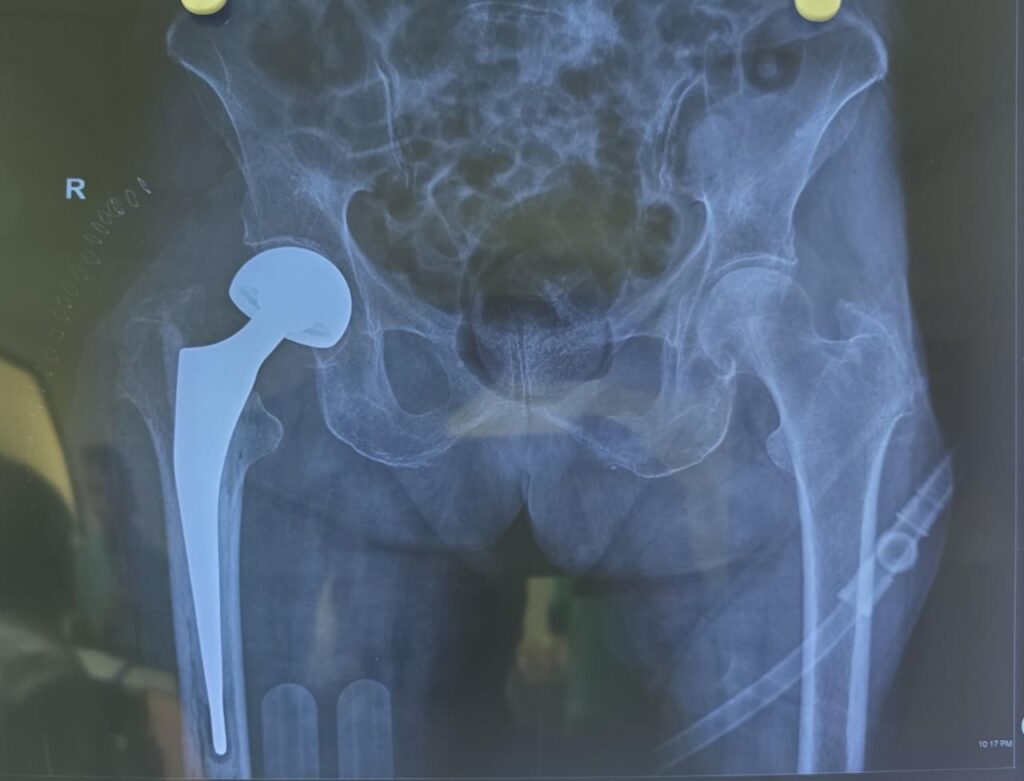

Robotic Joint Replacement Surgery

- Robotic Total Hip Replacement (THR)

- Revision Joint Replacement with Robotics

Conventional Joint Replacement Surgery

- Total Hip Replacement (Conventional)

- Revision Joint Replacement Surgery